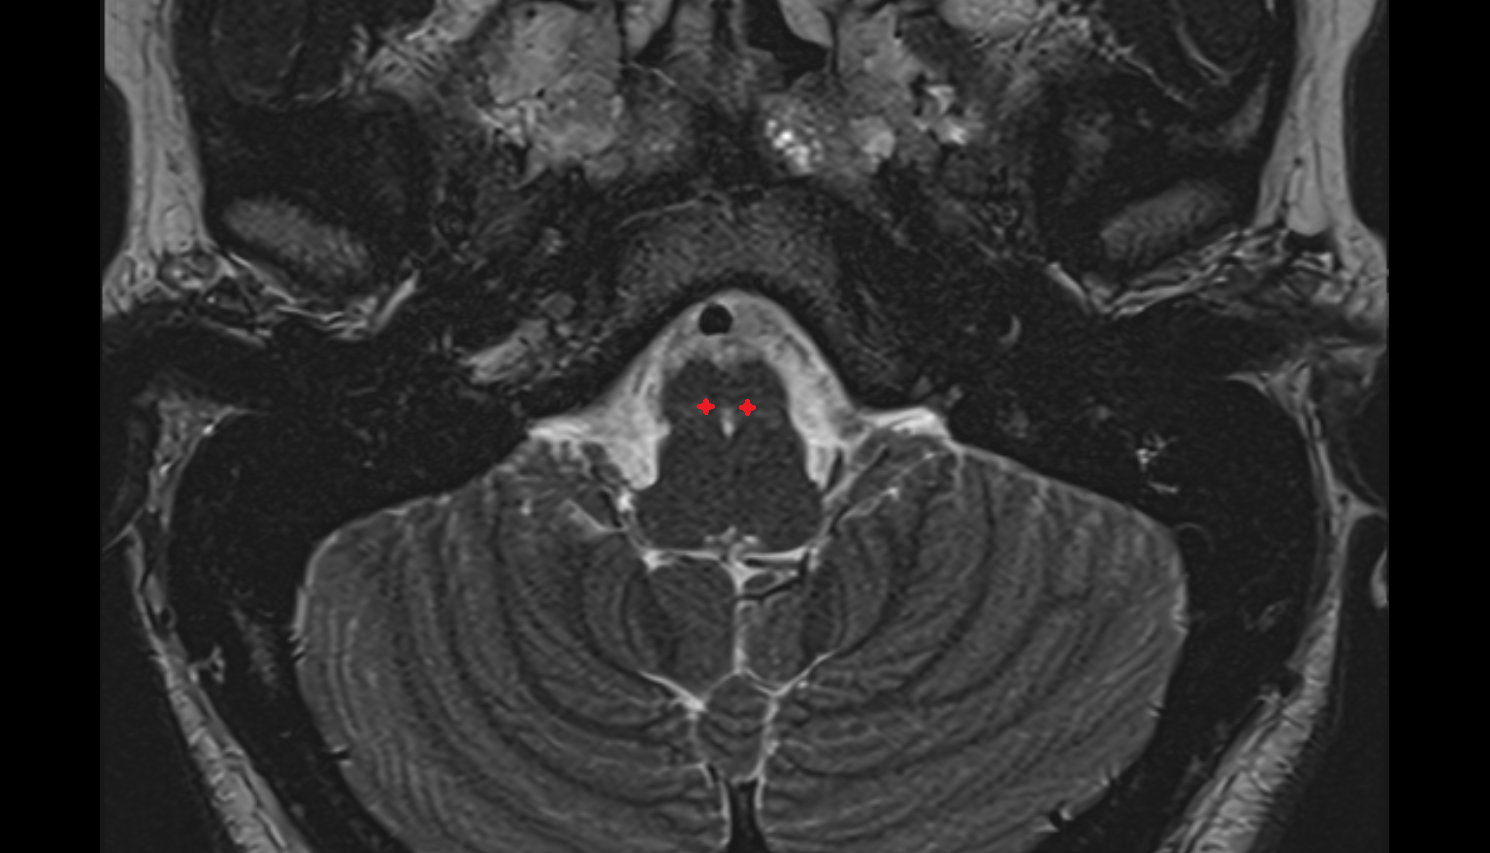

- Pons

- Median aperture of fourth ventricle (foramen of Magendie)

- Lateral aperture of fourth ventricle (foramen of Luschka)

- Cerebellopontine cistern